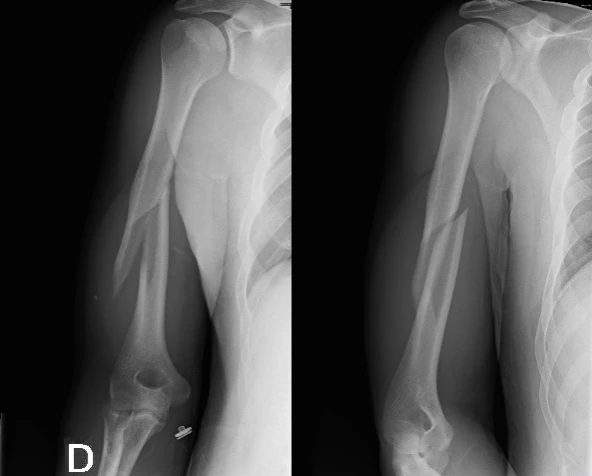

Le bras de fer, pratique sportive bien connue, n’est pas dénuée de risque ! Ce sont le plus souvent des lésions musculaires (épaule) et des douleurs articulaires (poignet, coude) qui surviennent, mais différentes fractures sont également décrites dans la littérature : fracture spiroïde de la diaphyse humérale (la plus fréquente, comme ici) avec parfois un fragment libre (butterfly fragment), fractures de l’épicondyle huméral médial, factures de la tête radiale avec luxation antérieure, voire fractures de la diaphyse radiale.

Des lésions de l’artère brachiale et du nerf radial peuvent être associée à de telles fractures humérales.

Lors du bras de fer, le coude est fixé à 90° environ par le muscle biceps brachial et le muscle brachial et un mouvement de rotation interne de l’épaule (contre l’adversaire) est appliquée principalement grâce aux muscles grand pectoral, sub-scapulaires et grand rond. Lorsqu’on commence à perdre le bras de fer, ces muscles de l’épaule subissent une contraction excentrique (se contractent tout en étant étirés puisque l’épaule du perdant se met progressivement en rotation externe). Ceci engendre une forte force de torsion sur l’humérus et peut-être la cause de fracture spiroïde de la diaphyse humérale.

Le traitement peut être conservateur (en l’absence de lésions associées) ou chirurgical.